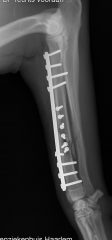

Wij komen regelmatig afwijkingen en ziekten van het steun- en bewegingsapparaat tegen. Ziekten aan het bewegingsapparaat worden vaak gekenmerkt door pijn; dieren komen niet overeind, bewegen minder of kunnen kreupel lopen. Soms is het noodzakelijk om röntgenfoto’s te maken om de oorzaak van de kreupelheid op te sporen. Hiervoor beschikken wij over een digitaal apparaat. Indien nodig kunnen röntgenfoto’s gemakkelijk met specialisten overlegd worden.

Vaak zal een bewegingsadvies gecombineerd met geschikte medicatie een oplossing bieden. In sommige gevallen zal een operatie noodzakelijk zijn om de klachten te verhelpen.